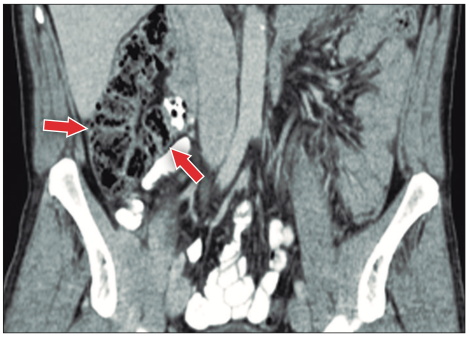

Posteriormente se realiza una tomografía computarizada de abdomen y pelvis sin contraste donde se observan asas intestinales dilatadas (Figura 1), ciego levemente distendido con abundante contenido propio, que cruza la línea media hacia el flanco izquierdo (Figuras 2 y 3), tracción e ingurgitación de los vasos mesentéricos (Figura 4).

Figura 3. Corte coronal. A: se observa ciego que cruza la línea media

para localizarse en el flanco izquierdo. B: ciego levemente distendido de aproximadamente 80

mm